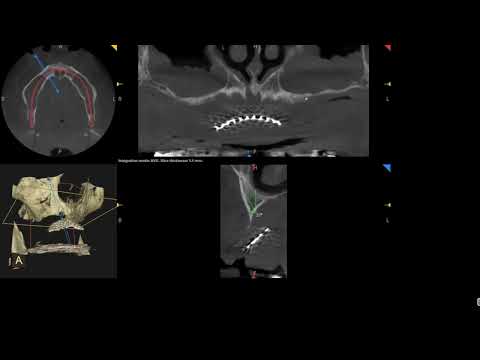

Hellow guys, Welcome to my website, and you are watching Double Pterygoid implant placement for severely resorbed upper full arch. and this vIdeo is uploaded by Learning Full Arch Implants - Only Surgery at 2018-02-22T03:25:24-08:00. We are pramote this video only for entertainment and educational perpose only. So, I hop you like our website.